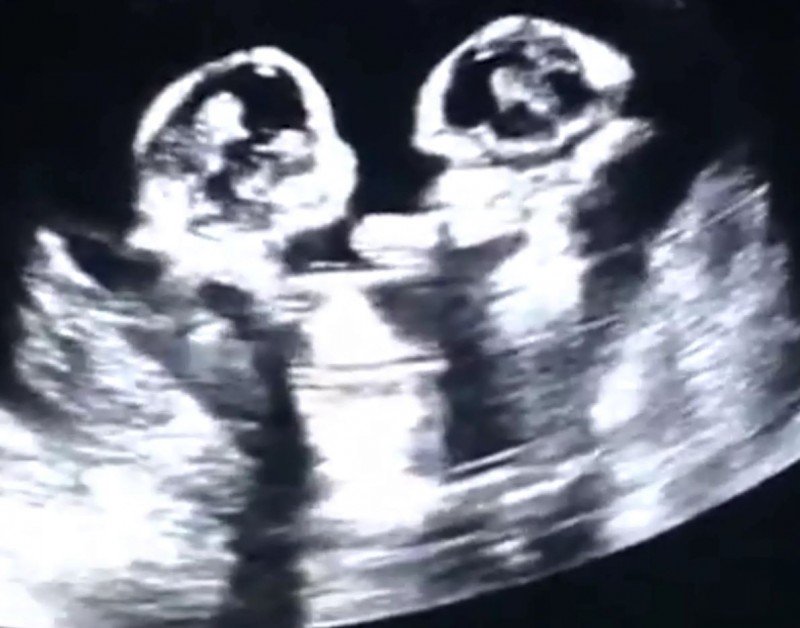

中國壹名孕婦懷了單絨毛單羊水的雙胞胎,兩個女嬰在子宮裡打架被超音波照了下來。(圖擷自微博)

中國寧夏銀川壹名孕婦,懷了3000萬分之1機錄的單絨毛單羊水(MCMA)同卵雙胞胎,先前產檢時醫生發現時腹內的兩個女嬰相當調皮,竟然互相出拳打對方,而這壹切都被超音波照了下來。

在照超音波時可以看到,左邊的女嬰率先發難,出拳打了右邊的女嬰壹下,被打的嬰兒也不甘示弱出手回擊,雙胞胎姊妹就這樣你來我往了好幾回。據了解,目前這對雙胞胎已成功剖腹出生,乳名分別叫小櫻桃和小草莓。- 新聞來源於其它媒體,內容不代表本站立場!